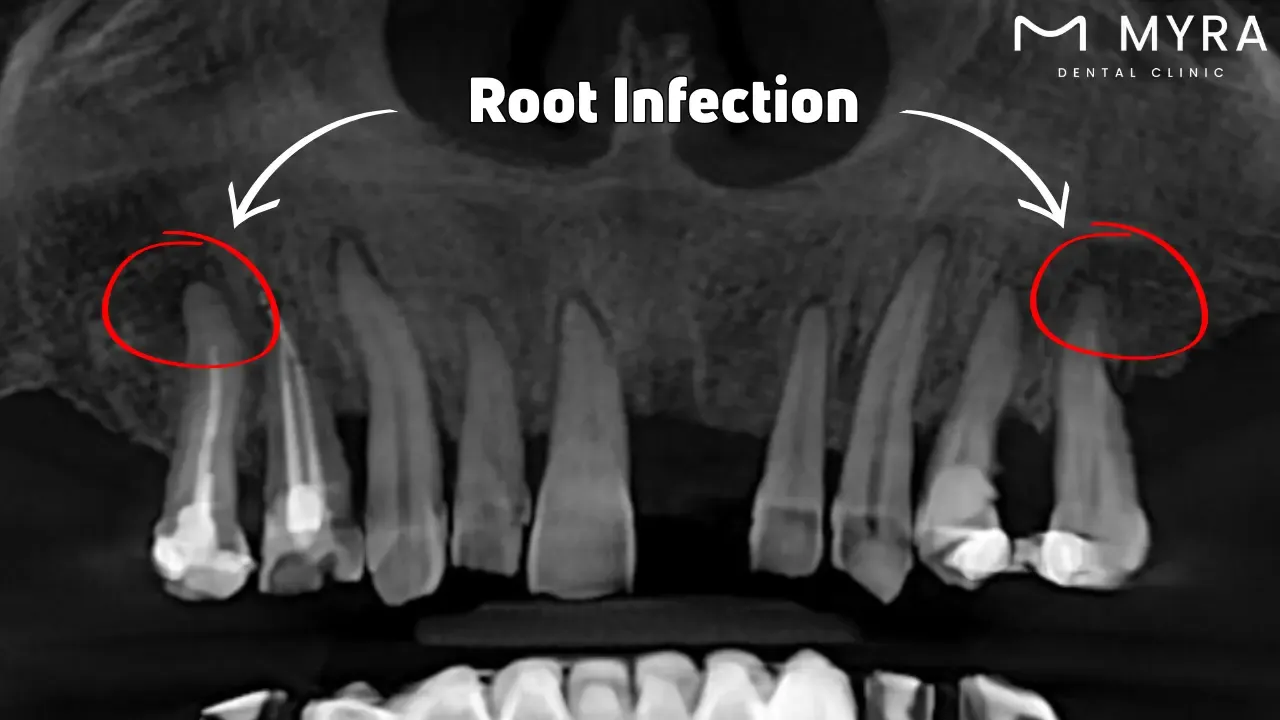

11. Root Infection

Root infection, periapical abscess, or dental abscess is caused by bacteria infiltrating the pulp, the innermost part of the tooth that contains blood vessels and nerves. The infection results in pus production and causes severe pain and swelling in the afflicted tooth’s vicinity. Serious dental diseases including root infections must be treated immediately to avoid problems.

Tooth decay, oral trauma, prior dental work, gum disease, and tooth wear and tear are among the main causes of root infections. A bacterial entry site is created by extensive tooth decay that extends to the pulp, resulting in an infection. It is frequently the result of bad oral hygiene habits that promote the accumulation of plaque and tartar. Pockets surrounding the teeth and retreatment of the gums are potential outcomes of advanced periodontal disease. The pockets get inflamed and result in a root infection if the germs reach the tooth's pulp. Severe wear and tear over time lead to enamel erosion and fissures, which raises the risk of pulp infection.

A root infection results in severe pain and discomfort, swelling and abscess formation, tooth loss, infection spread, and systemic health problems if left untreated. The excruciating, throbbing pain is caused by root infections while biting or chewing. The afflicted side's jaw, neck, or ears experience radiating pain. An abscess, or pocket of pus, develops from infection and causes significant swelling in the jaw, cheek, or face. The throat and neck are among the numerous regions where the swelling extends. A Root Infection erodes the surrounding bone and tissue when left untreated, causing loose tooth and falling out. The tooth disease spreads to other fatal body areas, such as the bloodstream (sepsis), sinuses (sinusitis), or jawbone (osteomyelitis). Chronic tooth infections have been related to various health issues such as respiratory infections, heart disease, and complications from diabetes because germs spread through the circulation.